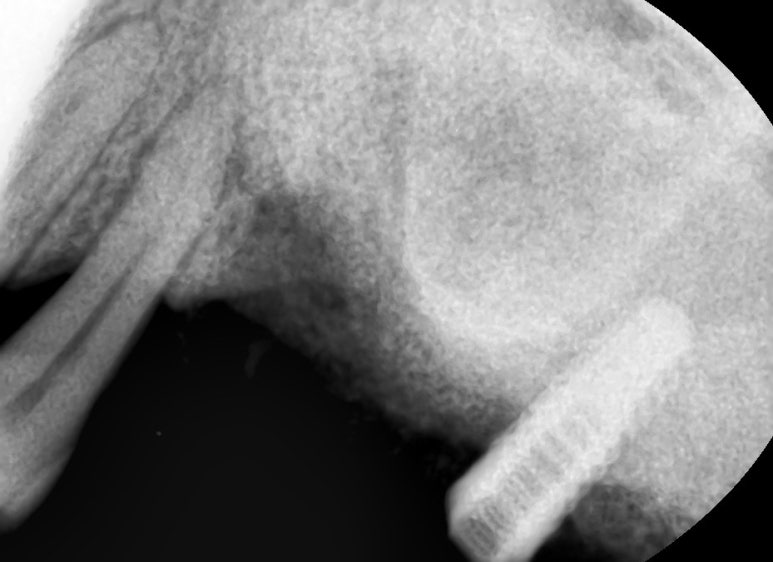

두 개 중 앞의 임플란트 제거후.

두개 중 앞의 임플란트는 많이 흔들리는 상태라 매우 쉽게 빠졌고

뒤의 임플란트는 뼈가 임플란트를 반만 잡고 있었지만

수술한지 오래된 임플란트라 잘 빠지지 않아 주변 뼈를 갈아내어 제거하였습니다.